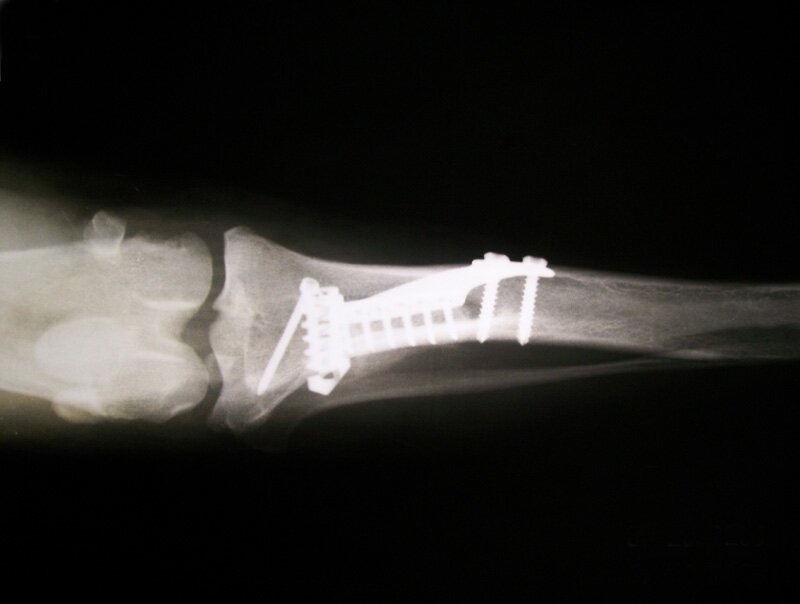

En la reparación de fracturas utiliza de forma habitual osteosíntesis mediante placas de compresión y tornillos, clavos cerrojados o técnicas tridimensionales de fijación externa.